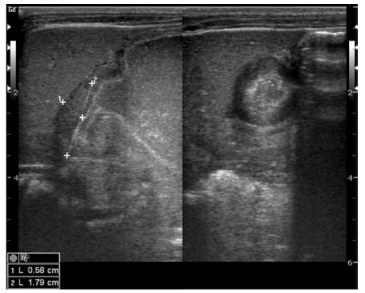

Mãe relata que lactente de 2 meses, alimentando-se exclusivamente de leite materno, vem

apresentando quadro clínico de vômitos em jatos,

não-biliosos, sem ganho de peso, com sinais

de irritação após a amamentação. Ao exame

físico encontra-se levemente desidratado +/+4,

anictérico, acianótico, com pequeno abaulamento

e massa palpável no quadrante superior direito.

Pediatra solicitou exame laboratoriais e avaliação

por imagem.

Considerando o quadro clínico e o exame de imagem, pode-se afirmar que: